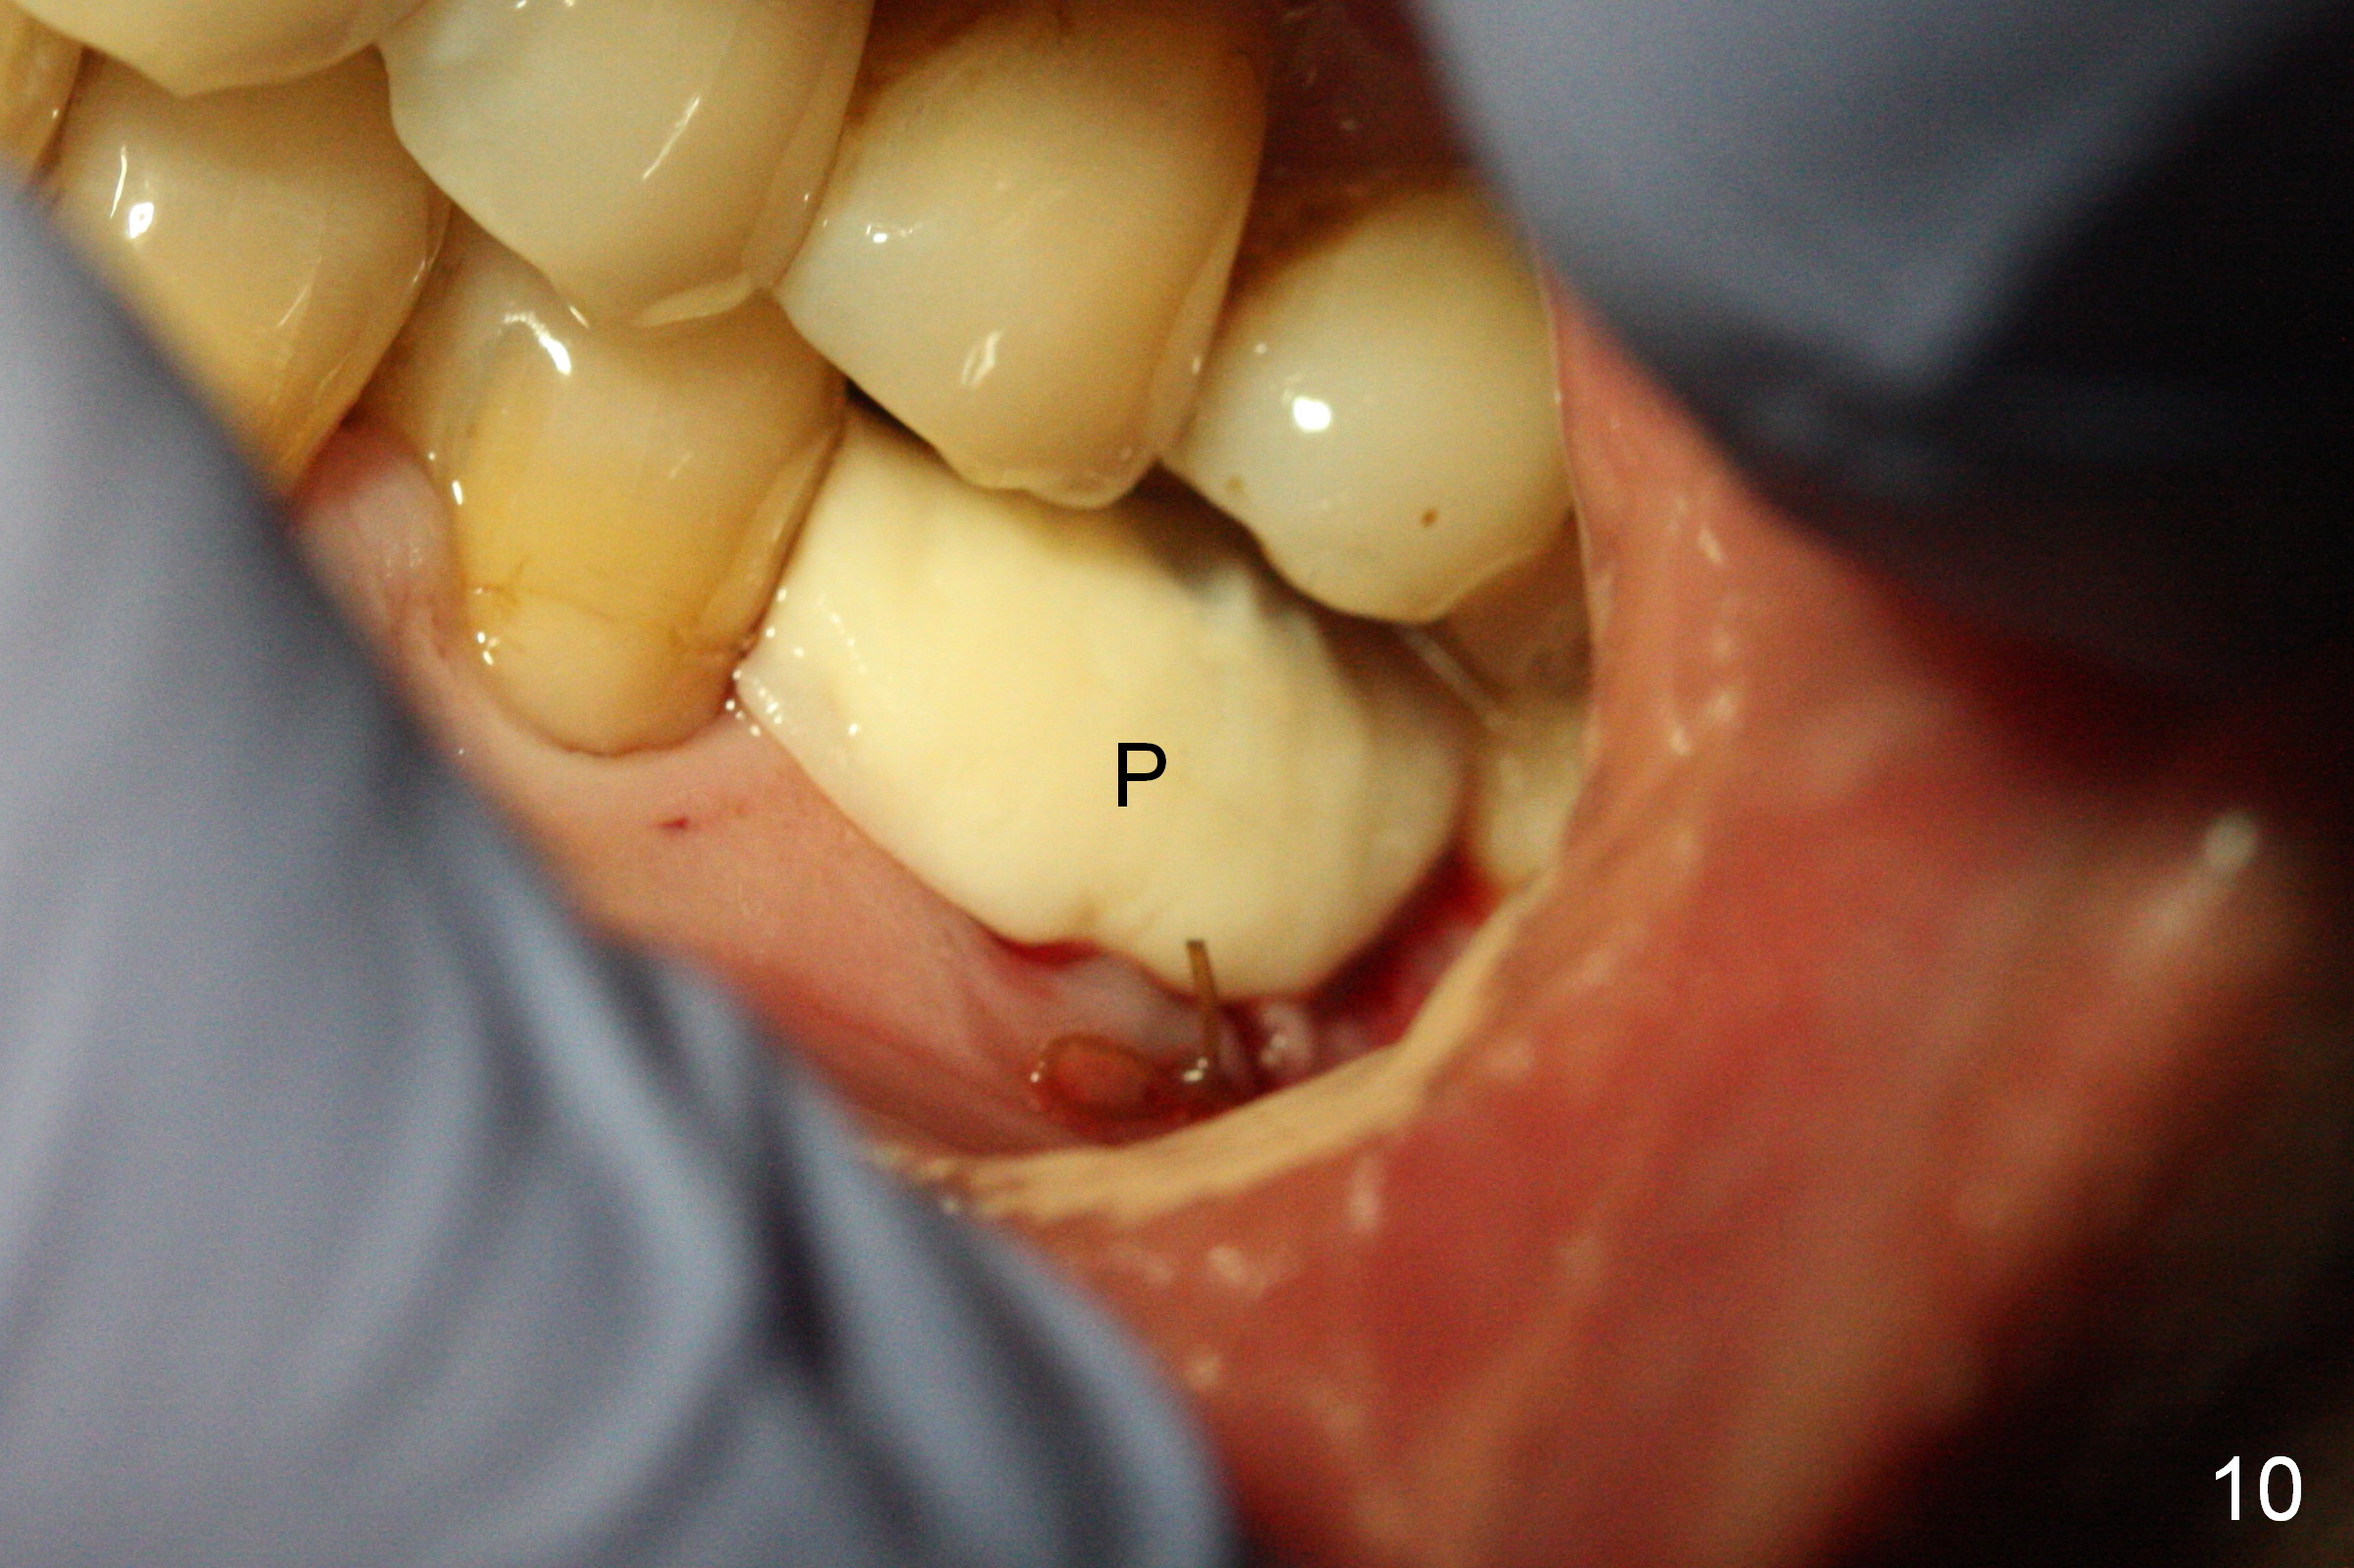

The asymptomatic tooth (#19) has a midbuccal fistula (Fig.1 <). The mesiobuccal pocket is 10 mm with purulent discharge from the sulcus (Fig.2,3). The mesiobuccal wall defect is confirmed when the tooth is extracted. Osteotomy is initiated lingually in the septum following septal crestoplasty (flattening) (Fig.4: using 1.6 mm drill for 9 mm). Since the lingual portion of the osteotomy is higher, it is difficult to use drill with stopper. For the narrow septum osteotomy, multiple drills are used sequentially (Fig.5 after 4.3 mm drill). A 4.5x11 mm dummy implant is placed (Fig.6) apparently too deep. When a 5x11 mm IBS implant is being placed, the depth is tightly controlled (Fig.7). The implant is apical to the lingual crest, whereas there is ~ 2 mm implant exposure buccally. That is, there is a large gap mesiobuccally (Fig.8), which is filled with .5-1.5 mm allograft (Fig.9 *). A 6.5x5.7(3) mm abutment (A) is placed and trimmed for an immediate provisional (Fig.10 P). The lacerated buccal gingiva is sutured as well as application of Perio Glue.